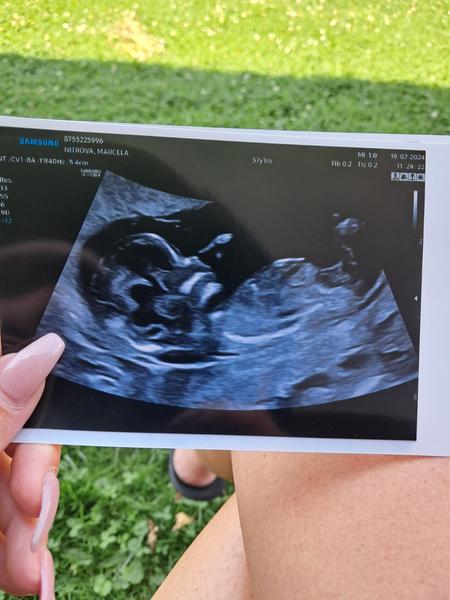

Holky jsem 14tt a podle ultrazvuku tipujete holka či kluk? 🙂

@marci1308 nevím, holka 😄✌️